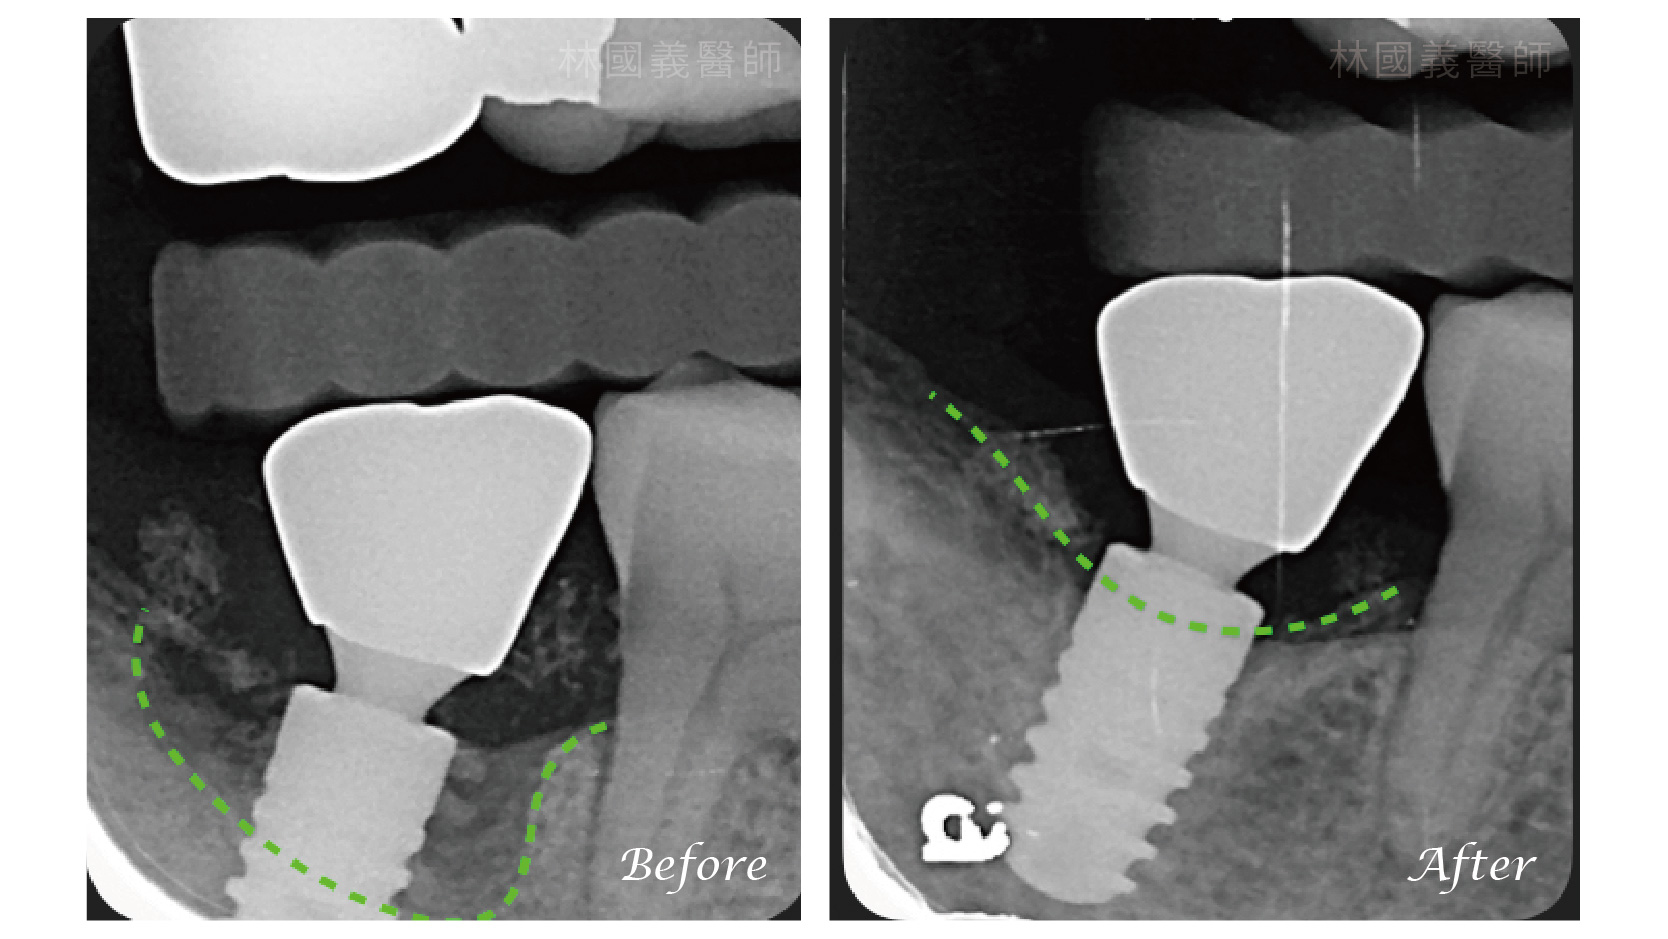

植體周圍炎 非手術治療|副院長 林國義 醫師